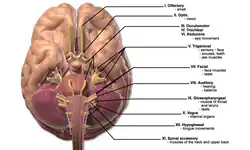

| This condition affects the cranial nerves | |

Neurosarcoidosis (sometimes shortened to neurosarcoid) refers to a type of sarcoidosis, a condition of unknown cause featuring granulomas in various tissues, in this type involving the central nervous system (brain and spinal cord). Neurosarcoidosis can have many manifestations, but abnormalities of the cranial nerves (a group of twelve nerves supplying the head and neck area) are the most common. It may develop acutely, subacutely, and chronically. Approximately 5–10 percent of people with sarcoidosis of other organs (e.g. lung) develop central nervous system involvement. Only 1 percent of people with sarcoidosis will have neurosarcoidosis alone without involvement of any other organs. Diagnosis can be difficult, with no test apart from biopsy achieving a high accuracy rate. Treatment is with immunosuppression.[1] The first case of sarcoidosis involving the nervous system was reported in 1905.[2][3]

Abnormalities of the cranial nerves are present in 50–70 percent of cases. The most common abnormality is involvement of the facial nerve, which may lead to reduced power on one or both sides of the face (65 percent resp 35 percent of all cranial nerve cases), followed by reduction in visual perception due to optic nerve involvement. Rarer symptoms are double vision (oculomotor nerve, trochlear nerve or abducens nerve), decreased sensation of the face (trigeminal nerve), hearing loss or vertigo (vestibulocochlear nerve), swallowing problems (glossopharyngeal nerve) and weakness of the shoulder muscles (accessory nerve) or the tongue (hypoglossal nerve). Visual problems may also be the result of papilledema (swelling of the optic disc) due to obstruction by granulomas of the normal cerebrospinal fluid (CSF) circulation.[1]